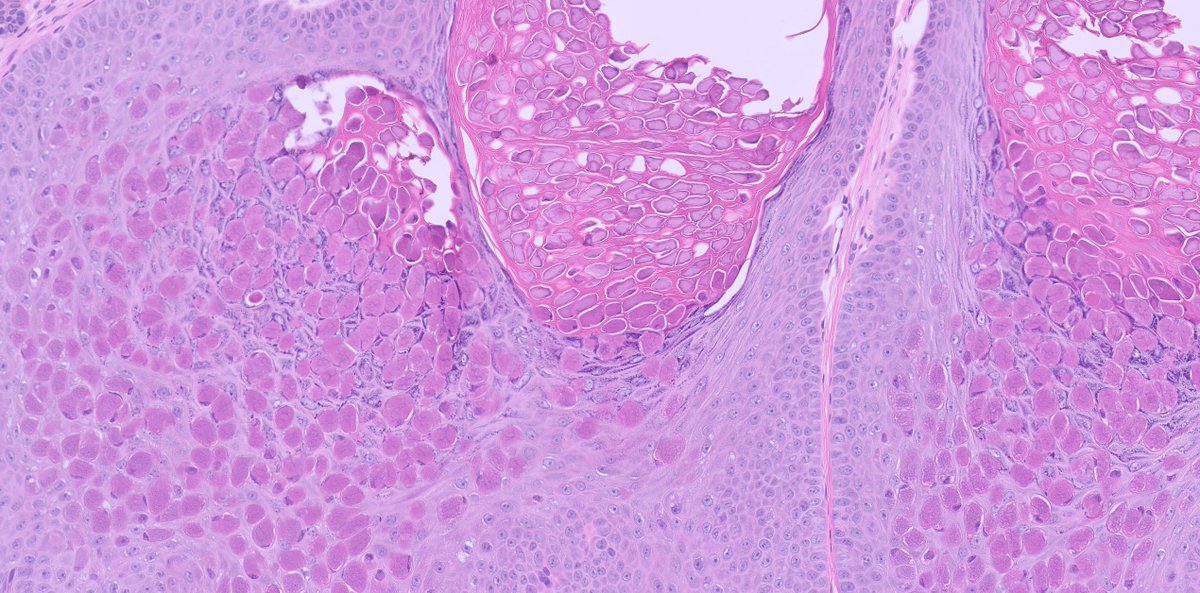

Syringocystadenoma papilliferum (SCAP) : ▫️Benign adnexal tumor ▫️cystic invaginations of the infundibular epithelium extending into the dermis with a double cell layer of inner columnar and outer cuboidal cells ▫️plasma cells are common in the stroma of each frond #dermopath